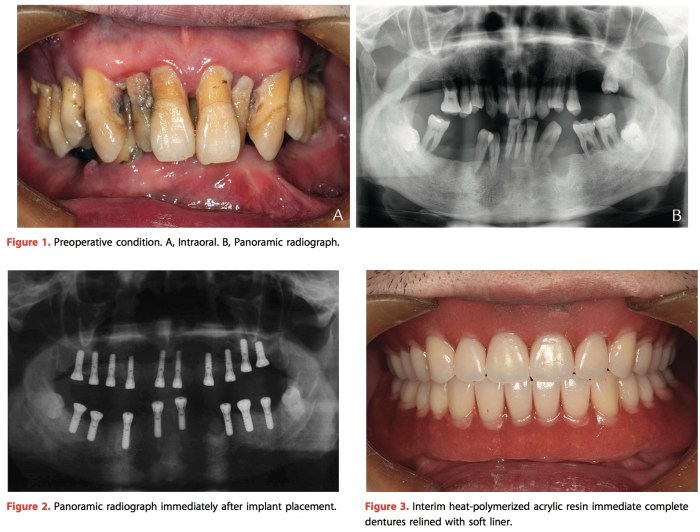

看圖說故事了~